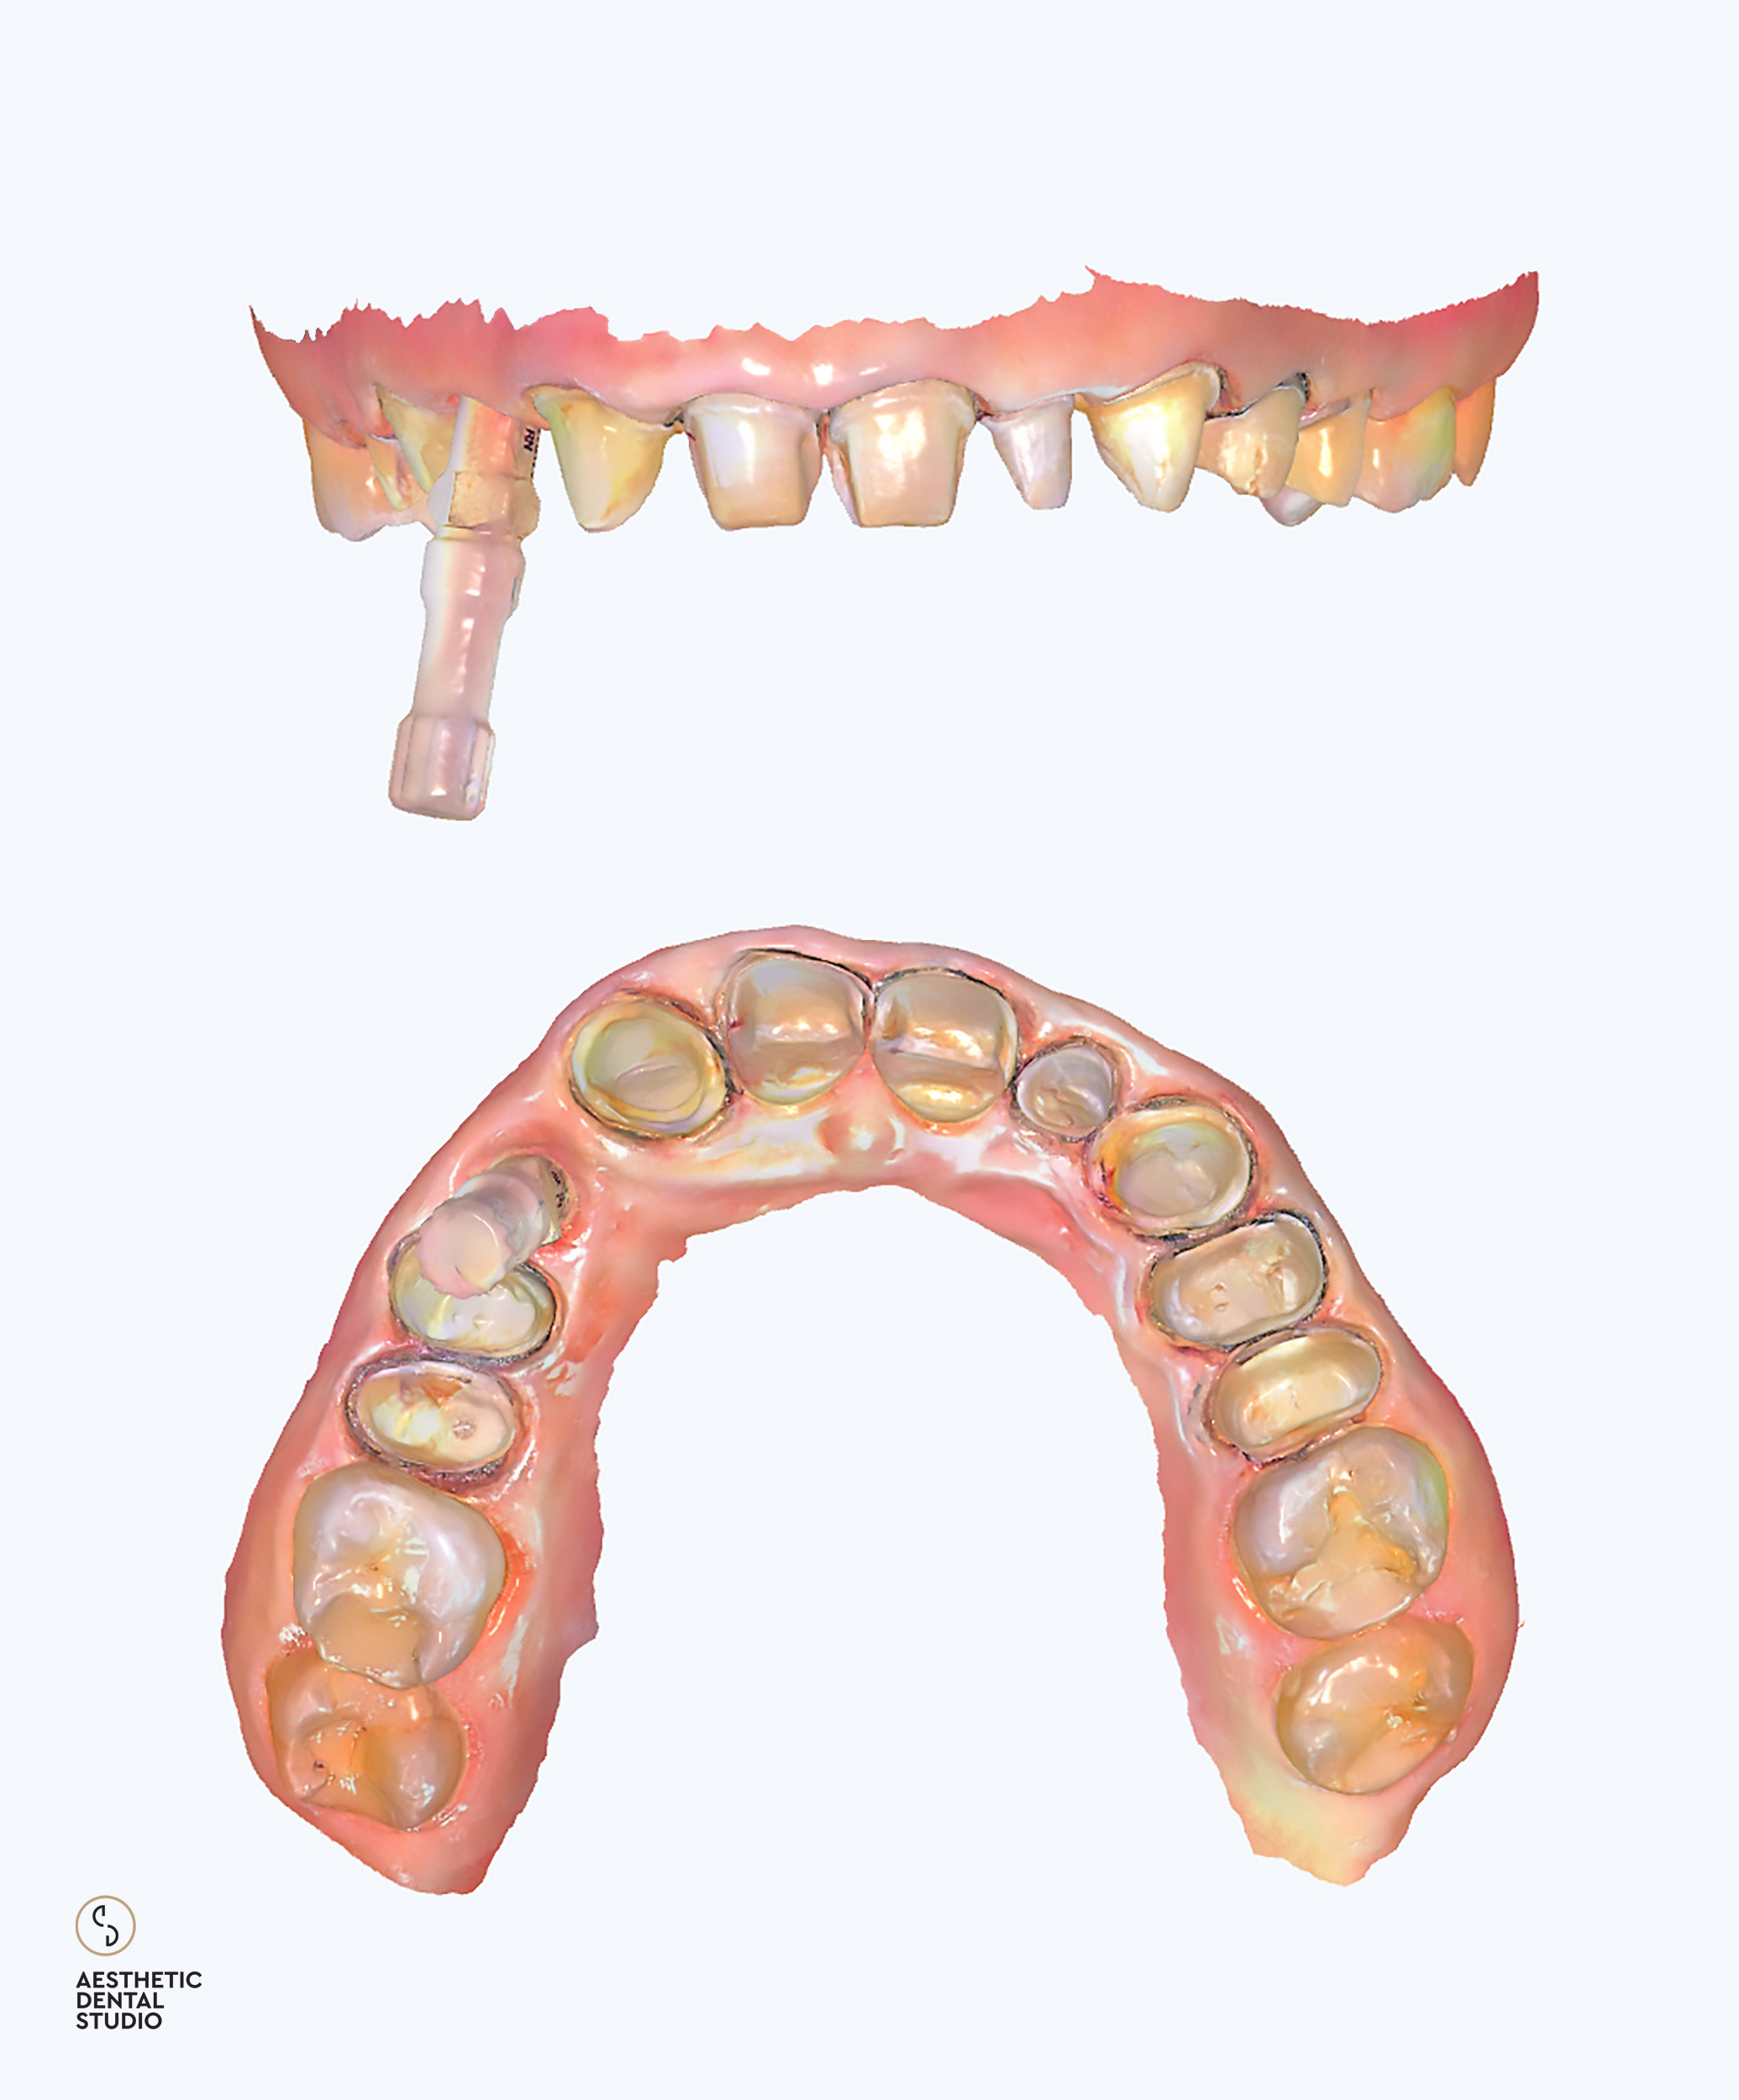

Το πρώτο στάδιο της θεραπέιας περιελάμβανε την ψηφιακή ανάλυση του χαμόγελου (Digital Smile Design), όπου με τη χρήση φωτογραφιών, βίντεο και ειδικού λογισμικού, σχεδιάστηκε το νέο χαμόγελο λαμβάνοντας υπόψη τις αναλογίες του προσώπου, των χειλιών και της φώνησης. Με βάση τον ψηφιακό σχεδιασμό, δημιουργήθηκαν διαγνωστικά εκμαγεία και προσωρινές αποκαταστάσεις, ώστε η ασθενής να δοκιμάσει το μελλοντικό της χαμόγελο πριν την τελική εφαρμογή.

Ακολούθησε η προετοιμασία των δοντιών και η λήψη ψηφιακών αποτυπωμάτων με ενδοστοματικό σαρωτή, τα οποία στάλθηκαν στο συνεργαζόμενο εργαστήριο. Εκεί σχεδιάστηκαν και κατασκευάστηκαν ολοκεραμικές αποκαταστάσεις υψηλής αισθητικής, με απόλυτη ακρίβεια εφαρμογής και χρωματική φυσικότητα. Οι τελικές όψεις και στεφάνες τοποθετήθηκαν στα δόντια της ασθενούς μετά από προσεκτικό έλεγχο αισθητικής, φώνησης και λειτουργίας, επιτυγχάνοντας απόλυτη εναρμόνιση με το πρόσωπο.